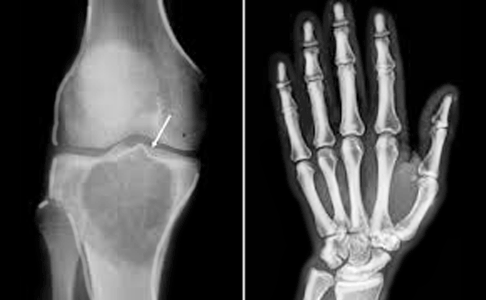

Radiografías simples de las articulaciones

(Clavícula, omóplato, mano, pie, dedos, huesos largos y mandíbula)

- Permiten la evaluación de fracturas, tumores, infecciones, alteraciones estructurales y enfermedades degenerativas.